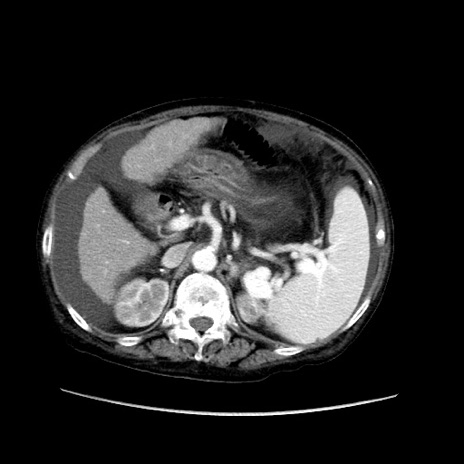

症例31(横断像)

【症例】80歳代 女性

【主訴】腹部膨満感

【現病歴】他院にて肝硬変にてフォロー中。1週間前から便秘、腹部膨満感、臍部腫瘤あり受診となる。

【既往歴】肝硬変

【身体所見】腹部膨隆あり、皮膚変化なし、疼痛なし。

【データ】WBC 4600、CRP 0.25